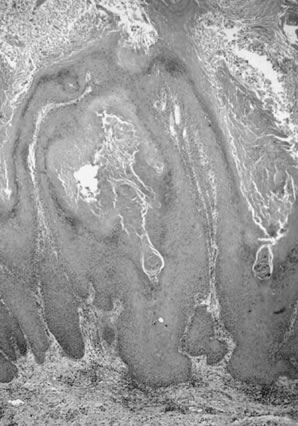

Verrucous carcinomas are an uncommon, special type of tumor with characteristic gross and microscopic features.42 Clinically, they are slow-growing, papillary, cauliflower-like lesions that eventually may become necrotic, ulcerated, and fungating.1,42 They may be locally destructive, and when surgically excised, they commonly recur but rarely metastasize. On histologic examination, verrucous carcinomas show a wartlike character similar to condylomata acuminata, demonstrating numerous branching papillary stalks composed of extremely well-differentiated squamous epithelium. Verrucous carcinomas are characterized by a “pushing” border with a well-defined tumor-dermal interface, without apparent infiltration.42 Cellular atypia is minimal and always restricted to the basal layer.42 Atypical mitotic figures are not identified and dyskeratosis and koilocytosis are absent. A chronic inflammatory cell infiltrate within the dermis is usually present. The lesion, called “giant condyloma of Buschke Lowenstein,” is now considered verrucous carcinoma.1 Verrucous carcinomas have been found to be associated with HPV, types 6 and 11 being the most common.43 These tumors are typically DNA diploid.

The main differential diagnoses for verrucous carcinomas include condyloma acuminatum and squamous carcinoma with verrucous features (warty carcinoma). Condylomata are typically not infiltrative, have prominent vascular dermal papillae separating the acanthotic epithelial elements, and have koilocytosis and dyskeratosis. Occasionally, VIN may occur within a condyloma, which can be distinguished by the nuclear pleomorphism and hyperchromasia, abnormal mitoses, and junction with the typical condyloma acuminatum. Warty squamous carcinomas have infiltrating tumors at the tumor-dermal interface (Fig. 13), rather than the pushing margins of verrucous carcinoma. Warty carcinomas usually have adjacent warty VIN, with koilocytosis, dyskeratosis, multinucleation, nuclear pleomorphism, and hyperchromasia. Usually abnormal mitotic figures are evident unlike verrucous carcinoma.

Fig. 13. Squamous cell carcinoma, warty or condylomatous type. The epithelium shows little cellular atypia and the tumor-dermal interface is infiltrative rather than pushing in appearance.